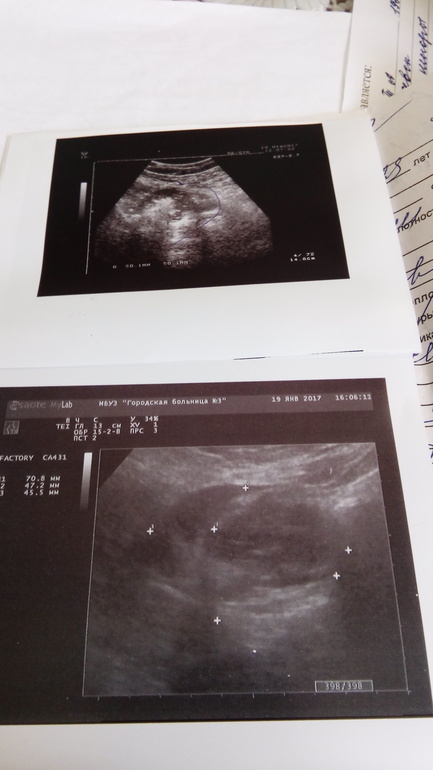

Могу ошибаться но по моему в заключении написано дермоидная киста правого яичника

УЗ-признаки объёмного образования справа. Вероятно дермоидная киста правого яичника

эндометрий не пойму какой???